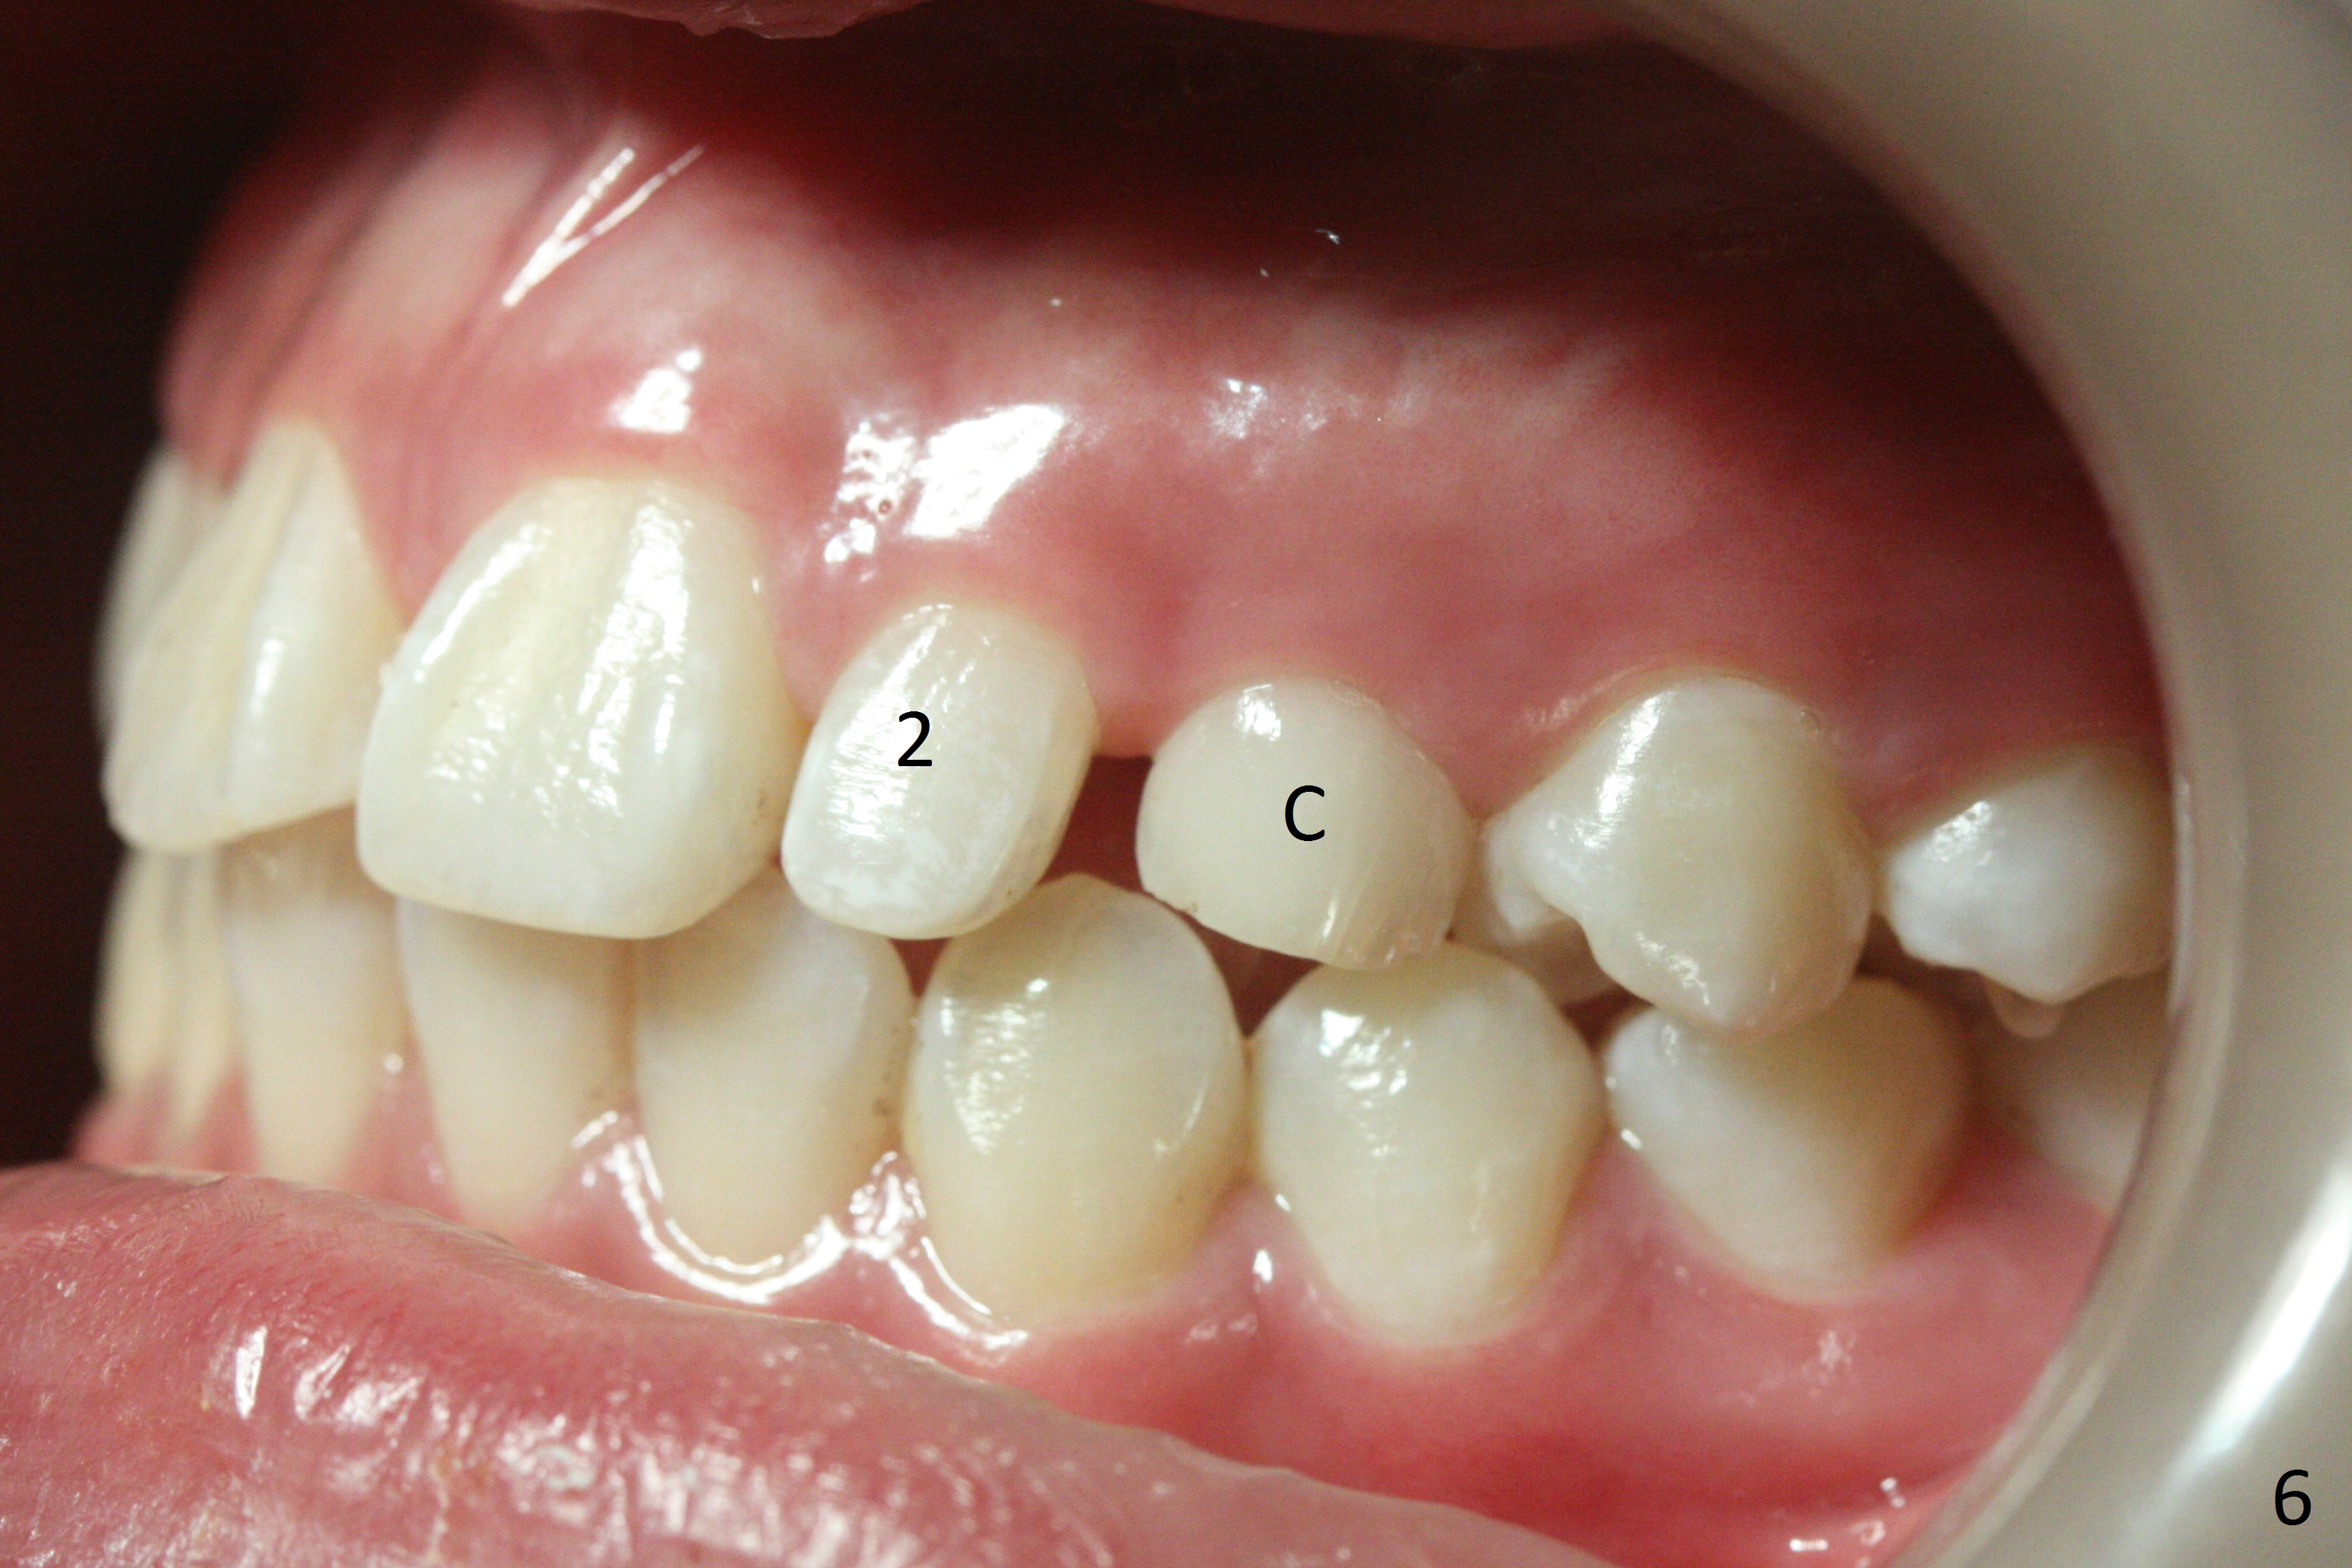

Two sisters (Sophia, 13 years old and Selina, 11) present to clinic for orthodontic treatment. Dental anomalies of Sophia include microdontia of the upper lateral incisors and congenital missing of the upper right permanent canine (Fig.5,6). For Selina, the upper right lateral incisor (Fig.5') and the upper left second bicuspid (Fig,6') are in cross bite.